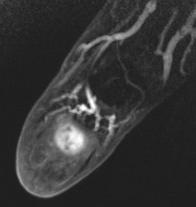

Tumeur glomique

Tumeur vasculaire bénigne de la dernière phalange

Tumeur hypervasculaire en IRM

Tumeur glomique de la dernière phalange